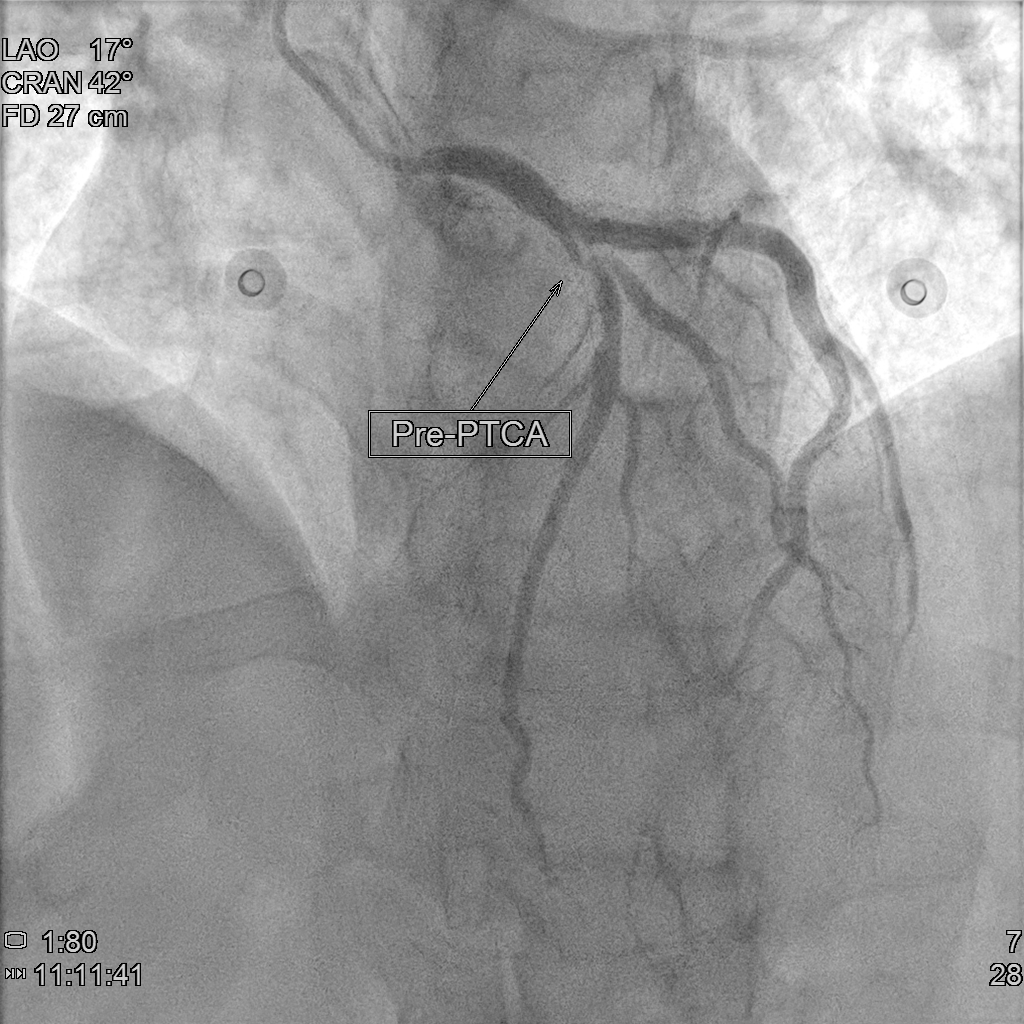

Coronary angiography showed CAD(1-V-D), with medina 1.1.1 bifurcation lesion at LAD-P and LAD-D1. We decided to performed provisional stenting strategy. We accidentally retracted the jailed wire after MV pre-dilation and TIMI flow of SB decreased to TIMI 1. It was difficult to rewire to SB due to acute take off angle after MV pre-dilation, so we performed DLC facilitated RWT. After that, we performed DK crush technique for the bifurcation lesion. The final angiography looks good.

Under support of Boston JL3.5,6Fr via Left Radial Artery approach, we introduced Floopy wire to LAD-D and Pilot 50 wire to LAD-D1. We dilated the 99% stenosis of LAD-M and LAD-P with Trek 2.5x20mm to 10 ATM. We checked the the intracoronary artery condition with IVUS and revealed severe stenosis and massive plaque burden in LAD-P to M and the lesion lenght of LAD-D1 orifice was 4.31mm with severe stenosis. After image evaluation, we used NC Trek 3.5x20mm to 12 ATM for predilatation, however, we incidentally retracted the LAD-D1 wire and we found that the flow of LAD-D1 became worse due to carina and plaque shift. It is challenging for direct wire and thus we perfomred reverse wiring technique with double lumen catheter (Crusade R). After that, we perfomred two stent strategy with DK crushing technique. We predilated the LAD-D1 with Trek 3.0 x15mm to 12 ATM. Then we deployed (NEW)SYNERGY XD 3.0 x20mm to LAD-D1, and crushed it with NC Trek 3.5x20mm to 12 ATM. Then we used CONQUEROR康克爾 4.0 x20mm to 20 ATM for POT followed by first kissing ballon technique with NC Trek 3.5x20mm to LAD and Trek3.0 x15mm to LAD-D1 to 8 ATM. After that, we deployed (NEW)SYNERGY XD 3.5x48mm to 12 ATM at LM to LAD-M. We performed POT with NC Trek 4.5x 8mm to 12 ATM followed by second KBT with the same balloones used during first KBT. We check the IVUS and performed the final POT with Trek 5.0 x12mm to 20 ATM due to malapposition noted at proximal site of stent. The final angiography looks good.